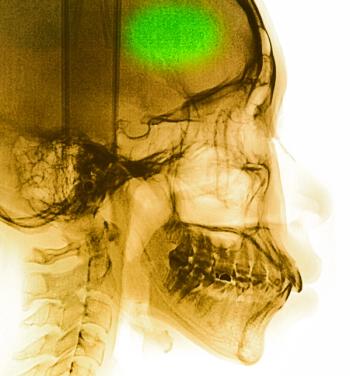

The patient reports the chest pain began 6 days ago during a vacation abroad. She denies any injury. What does the chest x-ray reveal?